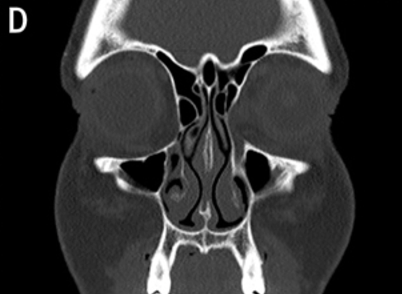

At VG Plastic Surgery, we carry out precise analysis and diagnosis procedures using 3D CT scans prior to surgery This is to analyze the problems that cannot be detected through consultation from a multi-faceted approach

An experienced plastic surgeon can determine the state of the nasal bone and the septal nasal cartilage based on a visual inspection alone. However, in order to determine the state of the nasal septum in the deeper parts, the degree of curvature of the nasal bone, the overall size and shape, and asymmetry, there is a need to perform a 3D analysis using 3D CT scans, which helps the surgeon formulate a more accurate and safer surgical plan. Of particular note, in the event of corrective nose surgery, a 3D analysis will reveal the state and notable characteristics of the implant and the septal nasal cartilage as well as the potential functional problems such as septal deviation in advance.

3D CT scans tailored to rhinoplasty procedures enable a multi-faceted analysis of the size and shape of the nasal bone, the septal nasal cartilage and the degree of curvature of the bone and/or cartilage and allow the surgeon to check for enlargement of the inferior nasal concha, presence of implants and determine the implant type and problems.